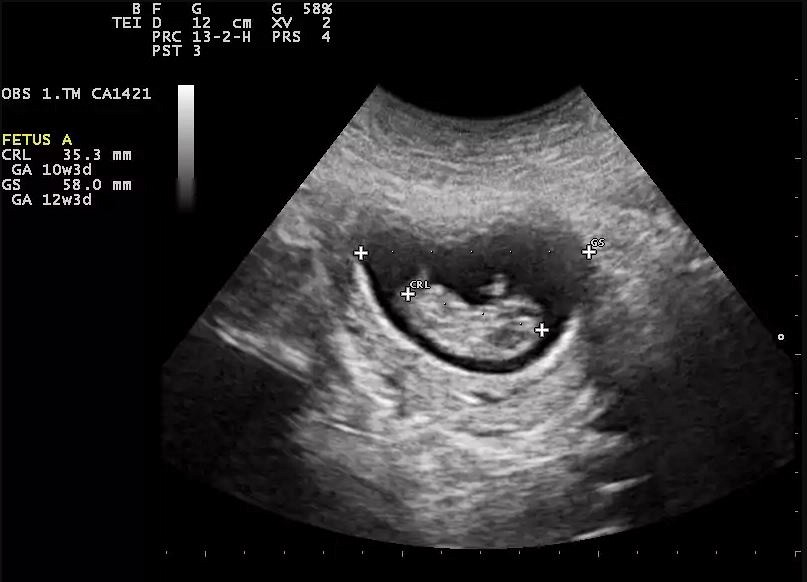

Parmi les études les plus marquantes publiées en 2022 que La Presse a listées dans son article "Une année de recherche en santé" du 26 décembre dernier rédigé par Mathieu Perreault, il y a entre autres, celle de Dr Frédéric Dallaire et de son équipe sur l’utilité de l’échocardiographie fœtale pour dépister les malformations cardiaques.